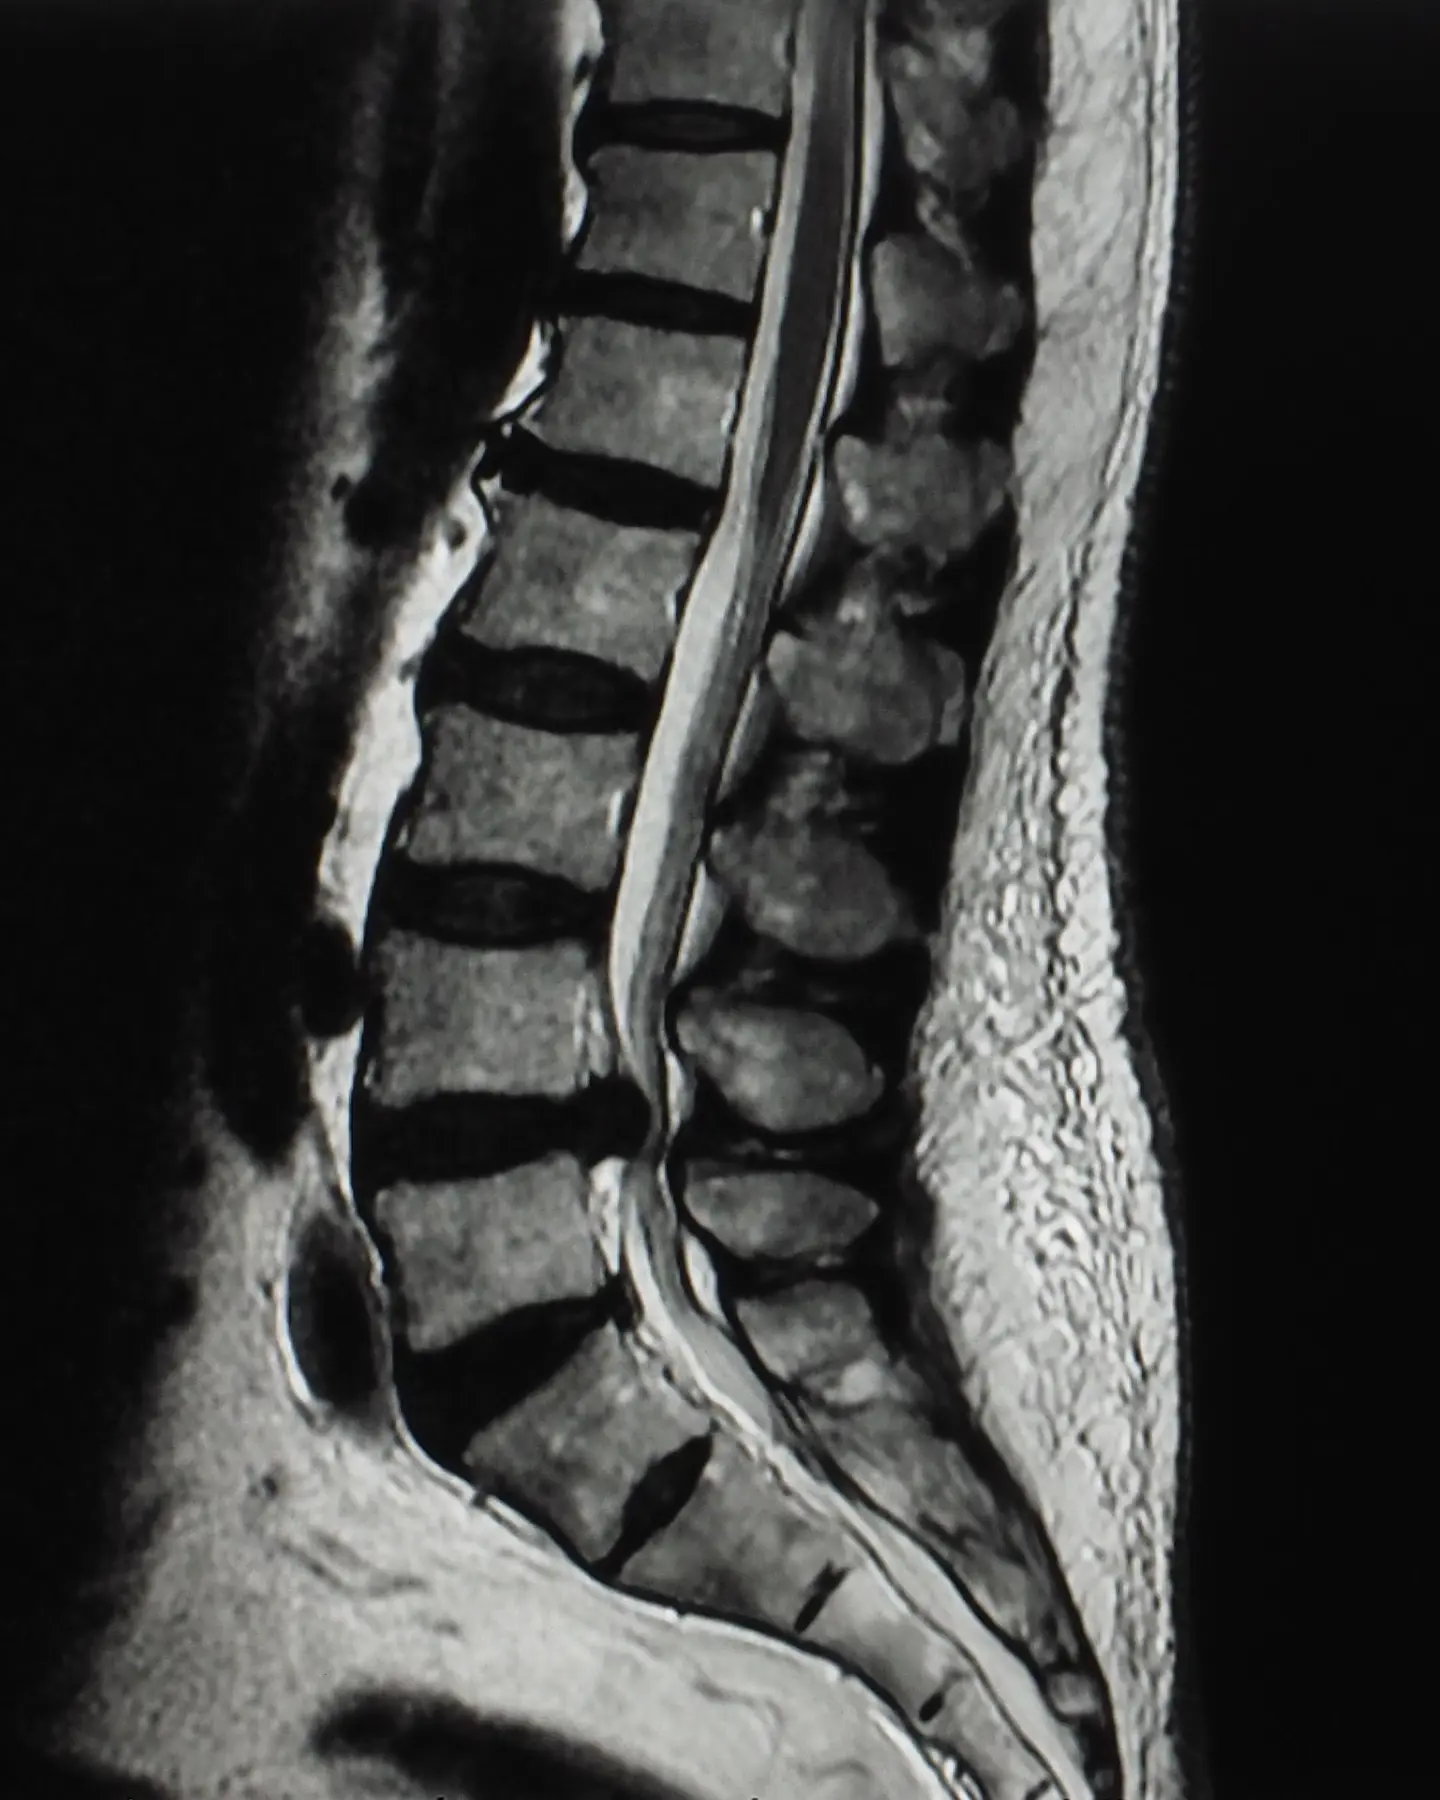

Diagnostic spine MRI scan

A spinal MRI scan can comprehensively assess the spine, including the lumbar, thoracic, and cervical regions, to identify any abnormalities or conditions affecting these areas.

A spine MRI scan can focus on one of three defined areas of the spine, depending on your symptoms and where you’re experiencing pain.